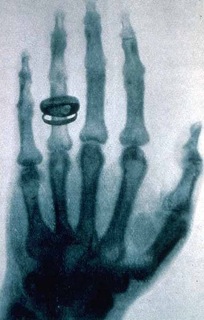

Mano vista con rayos equis

La longitud de onda de los rayos X, está en el ámbito entre una cien millonésima de metro y un valor mil veces menor. Es mucho menor que la longitud de onda de los rayos ultravioleta. Por consiguiente, los rayos X poseen mayor frecuencia y energía, lo que les permite atravesar cierto espesor de materia, como los tejidos de los seres vivos, para hacer radiografías, por ejemplo. Además, los rayos X pueden usarse para analizar la superficie de objetos y también para investigar la estructura interna de algunas sustancias.

El físico alemán Wilhelm Roentgen (1845 – 1923) fue la primera persona que observó y documentó los rayos x, el 8 de noviembre de 1895.